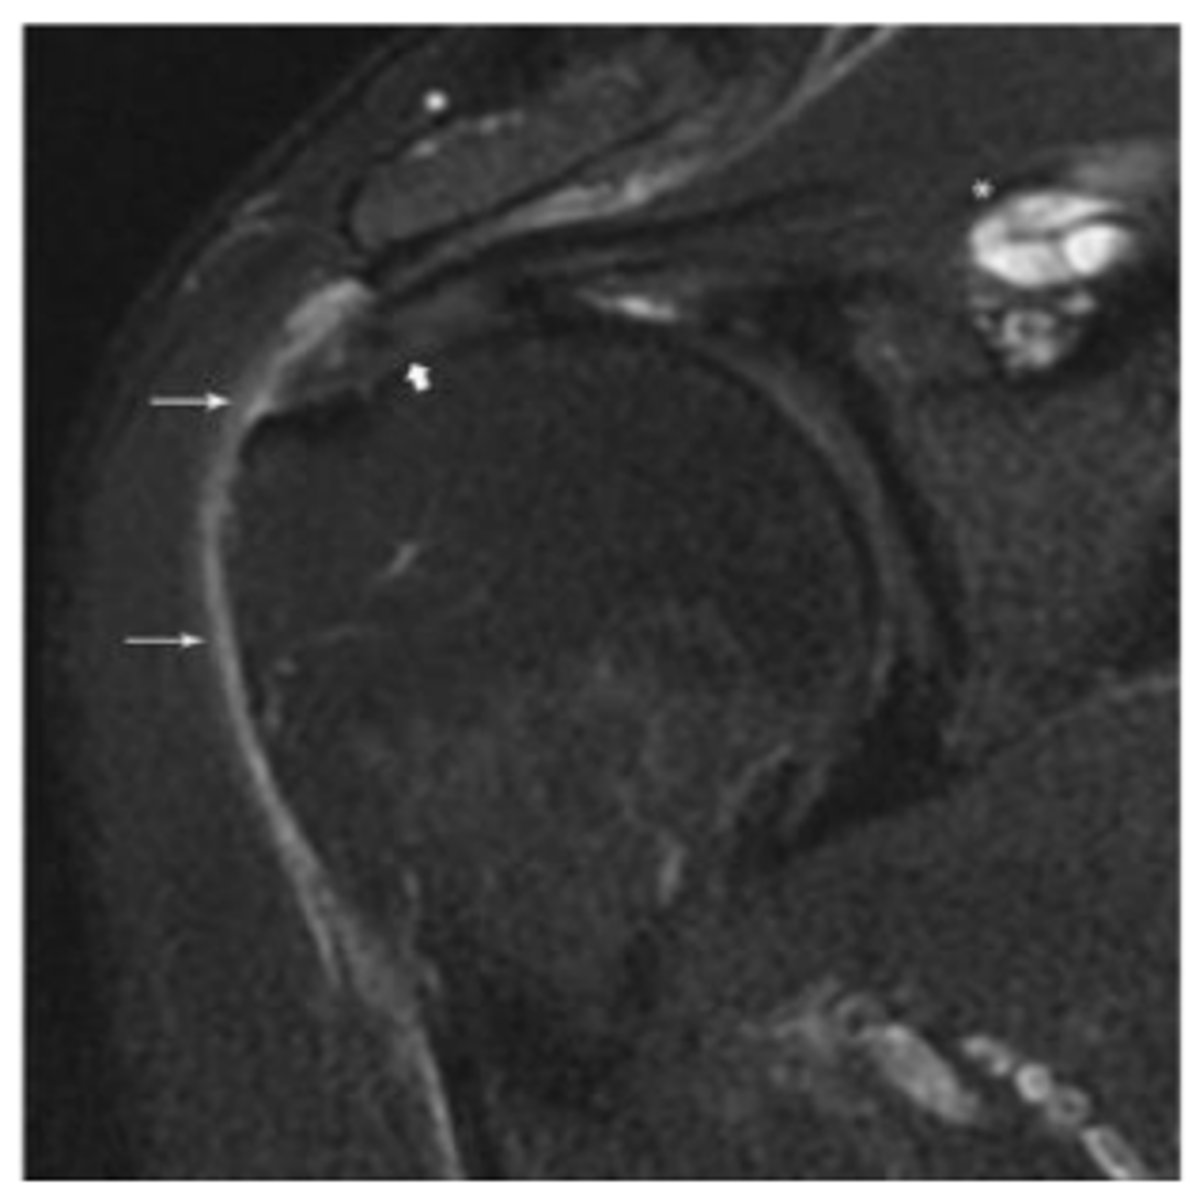

Thickening of supraspinatus tendon

What does the short white arrow show?

Small amount of fluid present in subacromial-subdeltoid bursa

What do the long white arrows show?

Supraspinatus intramuscular ganglion cyst

What does the asterisk show?

Minimally retracted full-thickness tear

What does the short arrow show?

Articular surface component with delamination

What does the long arrow show?

SLAP tear